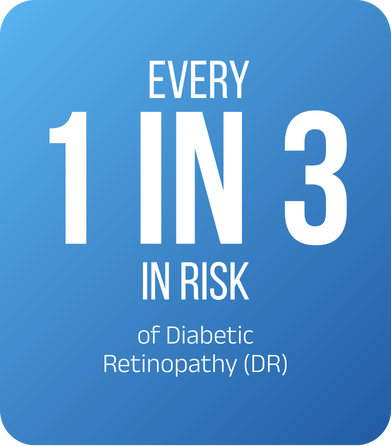

Fact :

- 1 in 3 risk of Diabetic Retinopathy (DR)

Diabetic Retinopathy (DR) is a silent epidemic in Bangladesh. With over 14 million people living with diabetes, studies show that 1 in 3 is at risk of developing DR. If left undiagnosed, this condition can cause irreversible blindness.